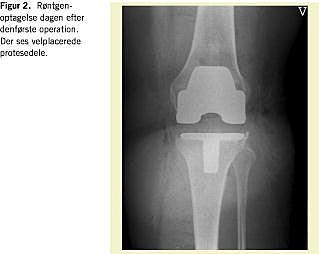

Indførelsen af antibiotika- og tromboseprofylakse ved ortopædkirurgi har mindsket hyppigheden hos overvægtige af alvorlige perioperative komplikationer til alloplastikbehandling. Langtidsresultaterne af alloplastikbehandling af disse patienter er dog generelt ringere end hos normalvægtige (Figur 1, Figur 2 , Figur 3 og Figur 4 ). Englund konstaterede hos meniskektomerede patienter med BMI > 30 kg/m2 en større hyppighed af knæ-OA end hos normalvægtige (BMI < 25 kg/m2 ) [16].